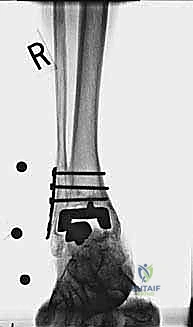

- الأشعة السينية مع تحميل الوزن (Weight-bearing X-rays): لتقييم الزوايا الميكانيكية وتحديد مدى هبوط المفصل أو وجود كسور في الكعب.

كسور الكعبين (Malleolar Fractures) المصاحبة للمفصل الصناعي

من أعقد التحديات التي تواجه جراحي العظام هي حدوث كسور في الكعب الداخلي (Medial Malleolus) أو الخارجي (Lateral Malleolus) في وجود مفصل صناعي. تحدث هذه الكسور لعدة أسباب:

1. ترقق العظام: حول المفصل الصناعي نتيجة لعدم استخدام الطرف بشكل طبيعي (Stress Shielding).

2. الاصطدام الميكانيكي (Impingement): إذا كان حجم المفصل الصناعي أكبر من اللازم، فقد يضغط على الكعبين من الداخل ويؤدي لكسرهما بمرور الوقت.

3. الإصابات المباشرة: مثل السقوط أو التواء الكاحل.

علاج هذه الكسور يتطلب مهارة فائقة من الدكتور محمد هطيف، حيث يتم استخدام تقنيات الجراحة الميكروسكوبية وتثبيت الكسور باستخدام صفائح معدنية دقيقة ومسامير (Locking Plates) دون المساس بثبات المفصل الصناعي، أو يتم دمج علاج الكسر ضمن عملية مراجعة المفصل الكلية إذا كان المفصل نفسه تالفاً.

الخطوة الخامسة: تركيب المفصل الجديد أو الدمج

يتم إدخال المفصل الجديد المخصص للمراجعة، والذي يحتوي غالباً على سيقان (Stems) تدخل عميقاً في عظمة الساق وعظمة الكاحل لضمان الثبات الميكانيكي. في حال وجود كسور في الكعب، يتم تثبيتها في هذه المرحلة.